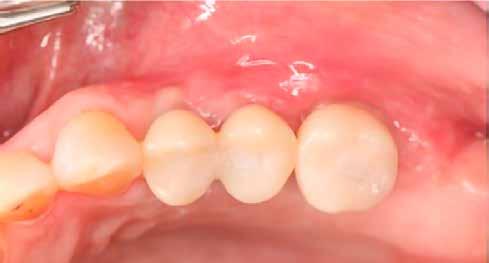

Egy 47 éves páciens jelentkezett nálunk egy alsó, hátsó foghiánnyal, ahol jelentős csontfelszívódást tapasztaltunk a moláris fogak korábbi eltávolítása miatt (1. ábra). Két implantátum körül is volt ínyrecesszió, illetve a keratinizált íny mennyisége minimális volt (kevesebb, mint 1 mm). 4 hónappal az implantációt követően ínykorrekciót végeztünk.

1. ábra: A műtét előtti szituáció, megfigyelhető az implantátumok közötti konkáv terület, ahova könnyen beragad az ételmaradék, és könnyen kialakul a periimplantitis.